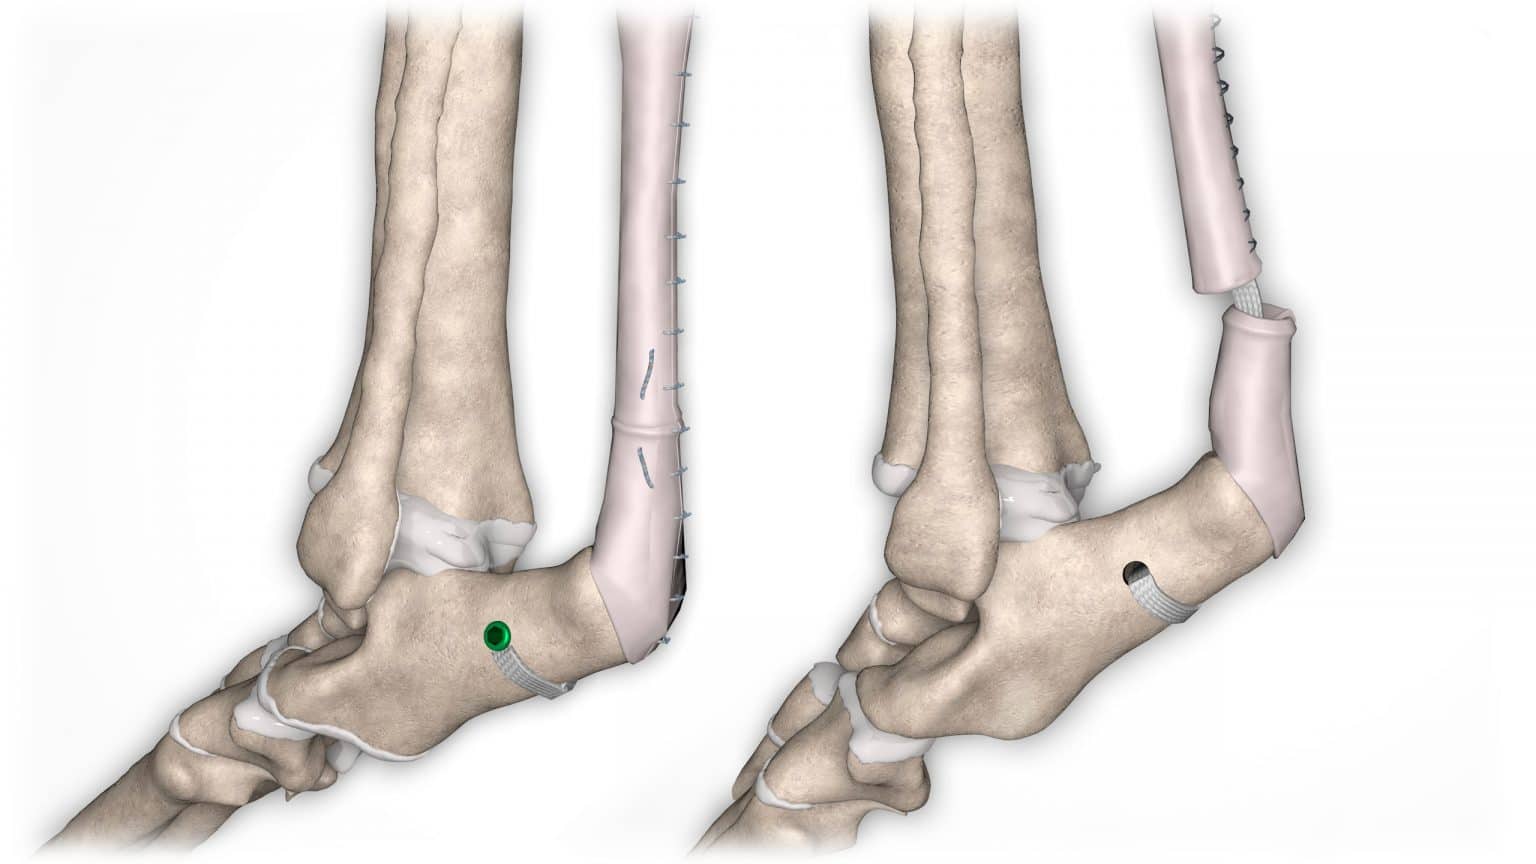

NOVALIG® je syntetický vaz, který lze použít k rekonstrukci vazů a rychlému obnovení jejich fyziologických funkcí.

V případě zkřížených vazů umožňuje intraartikulární rekonstrukci v izometrických bodech připojení, čímž obnovuje biomechaniku kolene a všechny funkce natrženého vazu.

V případě více vazů kolene (kraniální, kaudální, kolaterální) je možné pomocí NOVALIG® anatomicky rekonstruovat každý vaz.